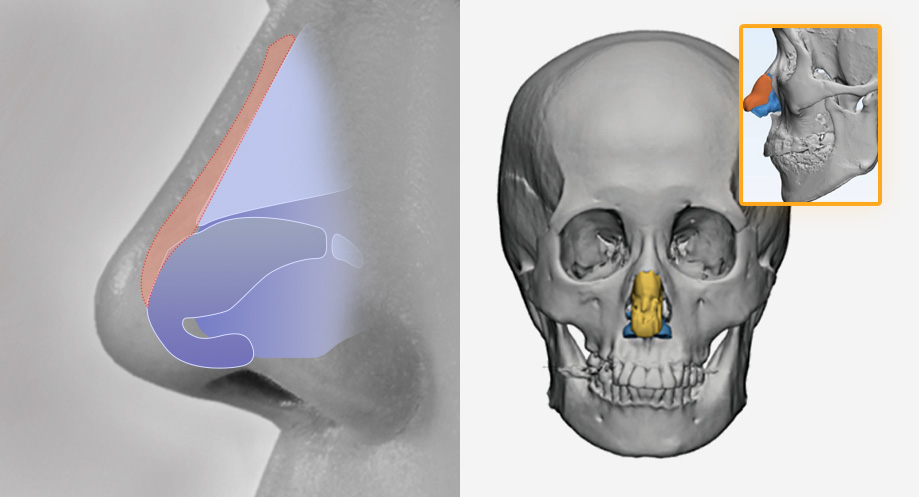

Conventional Rhinoplasty

Standardized mass-produced products

3D Rhinoplasty

Conventional Rhinoplasty

Standardized mass-produced products

3D Rhinoplasty